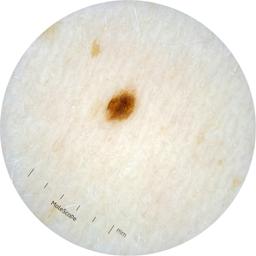

ISIC_2261268

acquisition_day 307

age_approx 50

anatom_site_1 Trunk

anatom_site_2 Posterior trunk

anatom_site_general posterior torso

diagnosis_1 Benign

diagnosis_confirm_type single image expert consensus

image_type dermoscopic